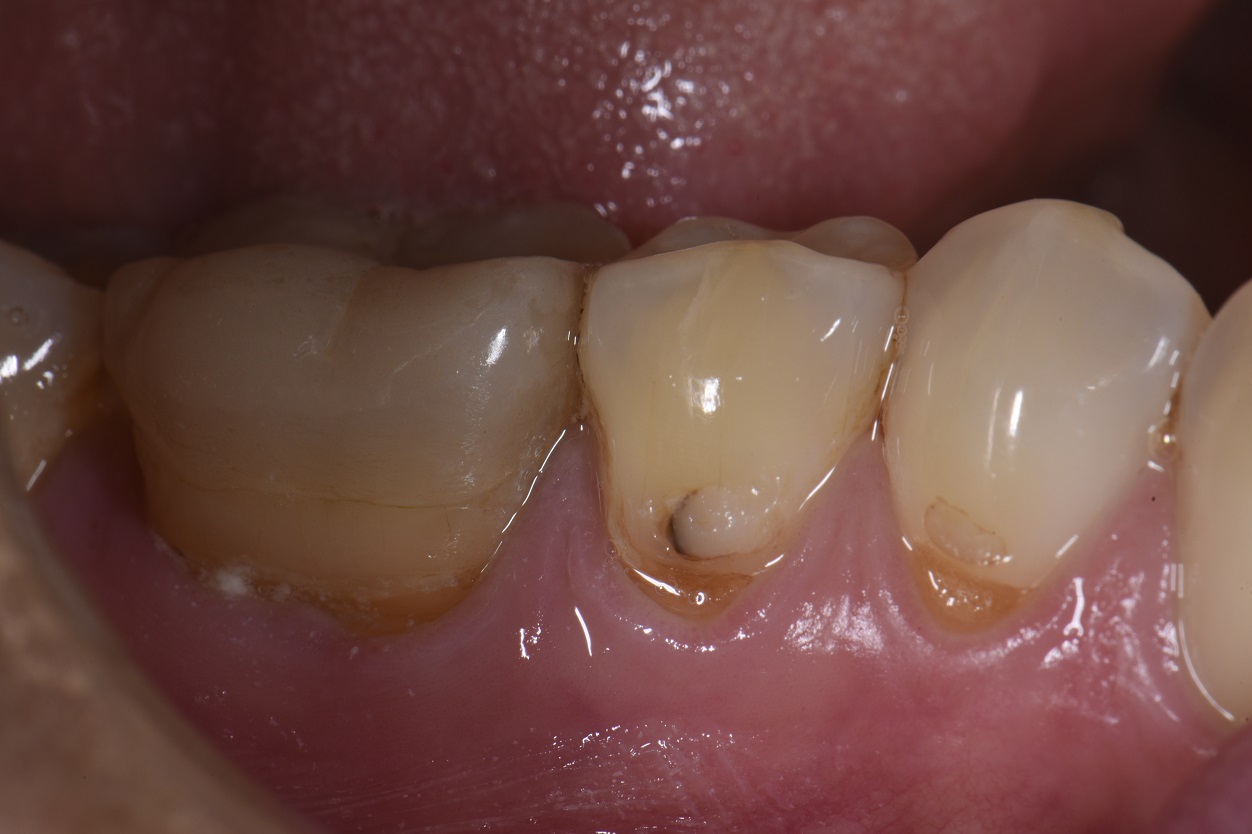

Extensive Class V restorations ahead of freehand direct coronal

Extensive Class V restorations ahead of freehand direct coronal What Is A Class V Restoration In Dental — class v cavities are multifactorial in origin. The class v with subgingival. — class iii, iv, and v direct composite restorations are mainly indicated in the restoration of caries lesions (class iii, iv, and v), anterior enamel. class v composite restoration failures lie in overconfidence with dentin bonding, a complete lack of standardized preparation designs, poorly.. What Is A Class V Restoration In Dental.